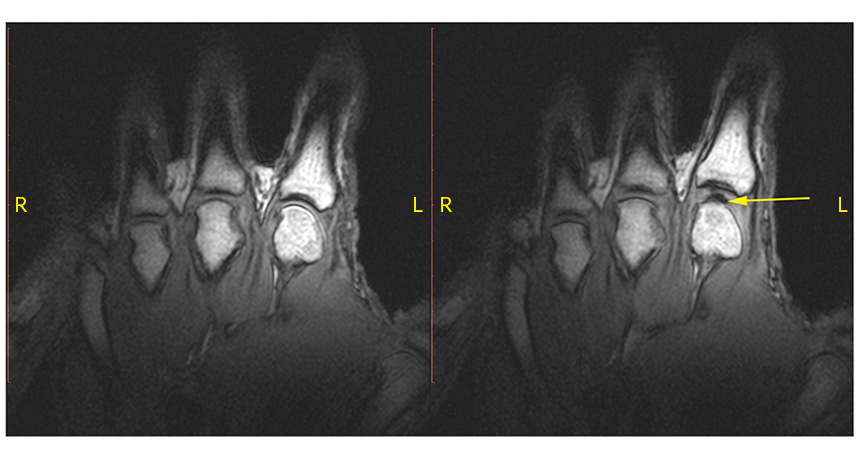

KNUCKLING DOWN  A knuckle at rest (left) pops when pulled. The sound of the knuckle cracking comes from a bubble (right, arrow) opening in the joint.

G.N. Kawchuk et al/PLOS ONE 2015 (CC BY 4.0)

Knuckles crack when a bubble forms in a joint, new high-speed images reveal.